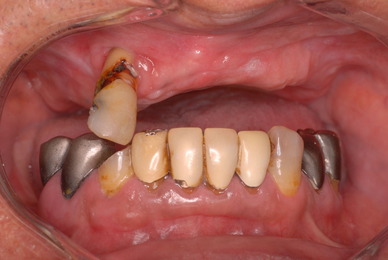

上の歯は一本がブラブラでしたね。

カビのような汚い部分を除去した直後です。